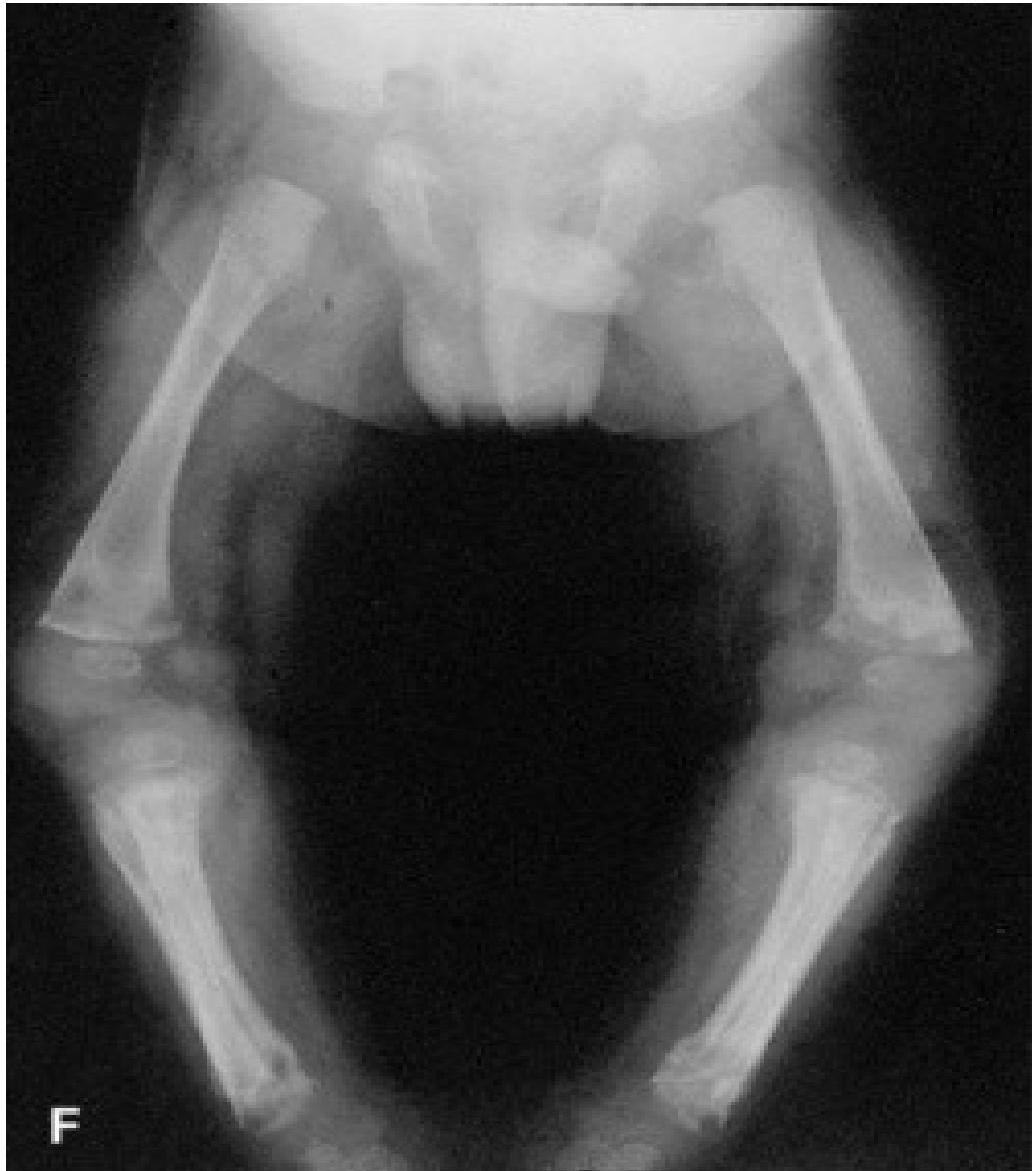

- Bone changes: periostitis, osteochondritis → pseudoparalysis.

Periostitis of long bones seen in neonatal syphilis

- Radiology: metaphyseal changes, periostitis.